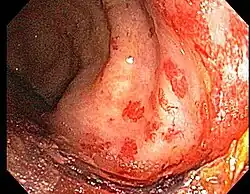

Chronic radiation proctitis

- Chronic Radiation Proctitis

- Etiology: obliterative endarteritis and chronic mucosal ischemia, leading to progressive epithelial atrophy and fibrosis. Ultimately, development of a chronically ischemic intestine prone to fibrosis and bleeding

- Symptoms: diarrhea, obstructed defecation (if strictures), bleeding, rectal pain, rectal urgency, and fecal incontinence. Rarely fistulas, SBO

- Diagnosis: colonoscopy, barium studies if suspecting strictures and fistulas